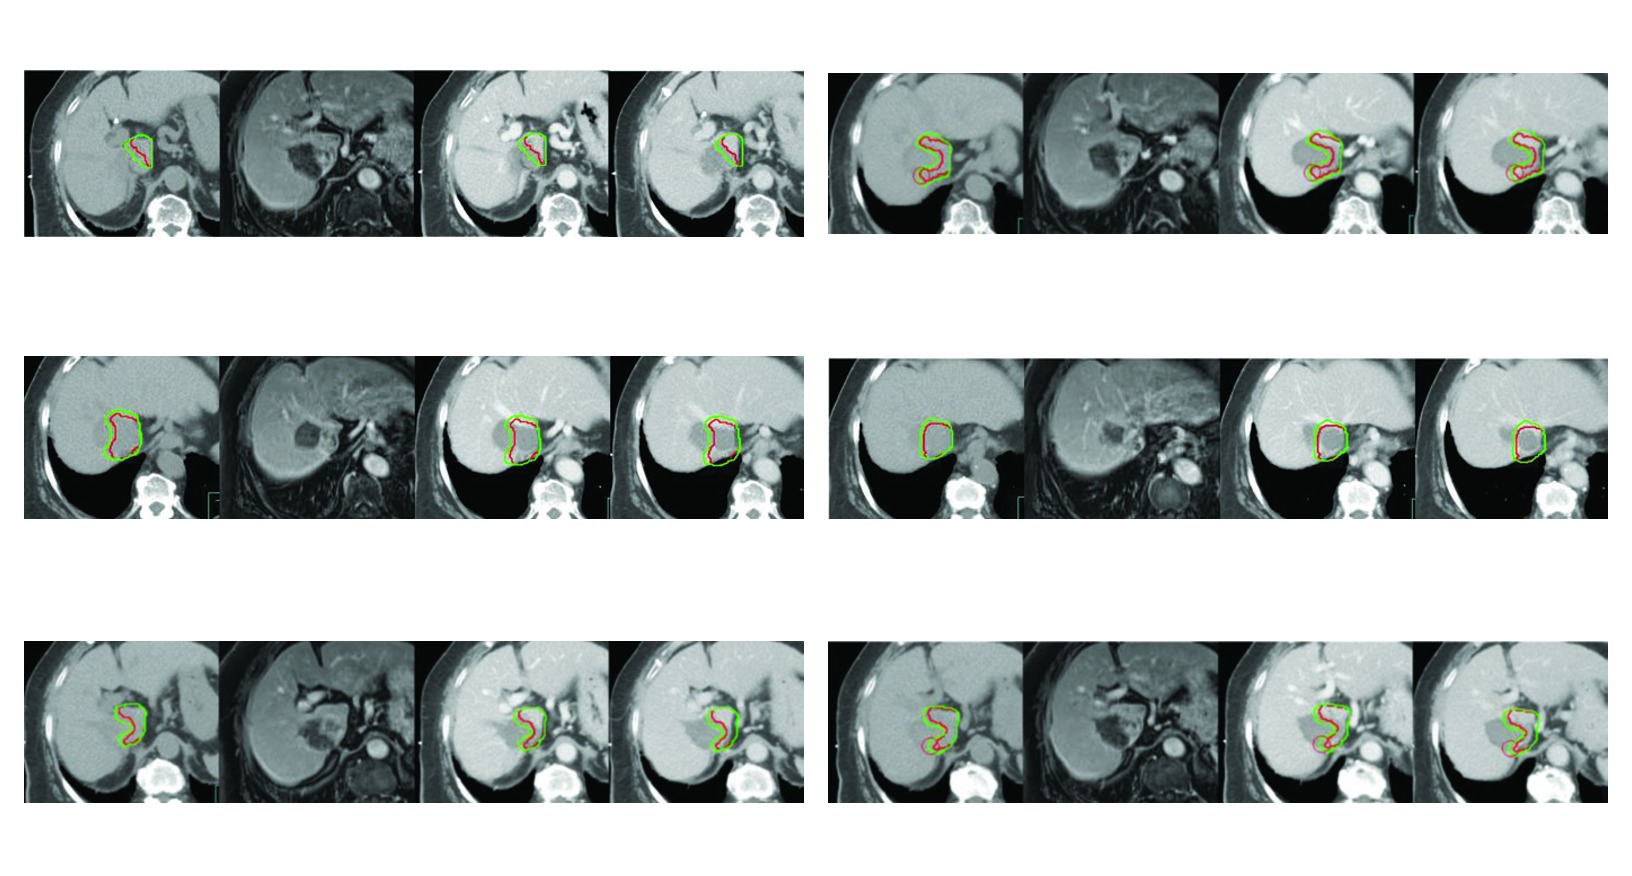

A Figura 17.2 reforca por que esse cuidado e central. O caso de recorrencia com trombose parcial da veia cava inferior apos radiofrequencia repetida so se torna bem delimitado porque a simulacao trifasica foi obtida com coordenacao de apneia para imobilizacao hepatica. O CTV inclui o tumor contrastado, o trombo tumoral visto como GTV e ainda uma margem de 5 mm ao redor do GTV dentro do limite do figado e da zona previamente ablada quando isso e clinicamente necessario. E um excelente exemplo de movimento e historia de tratamento alterando o volume final.

As quatro figuras do capitulo funcionam como exemplos aplicados da mesma logica. Todas usam simulacao multiphasica com coordenacao de apneia para imobilizacao do figado. Todas mostram GTV em vermelho e CTV em verde. E todas deixam claro que a margem muda quando entram em cena trombo tumoral, zona previamente ablada, area embolizada ou risco de extensao ao longo do vaso.

Figura 17.2

No segundo, a recidiva apos radiofrequencia repetida mostra como o volume pode incluir o leito previamente tratado quando ha necessidade clinica. A margem de 5 mm ao redor do GTV dentro do figado e da area ablada nao representa excesso. Ela reflete risco contiguo dentro de um contexto de tratamento anterior.